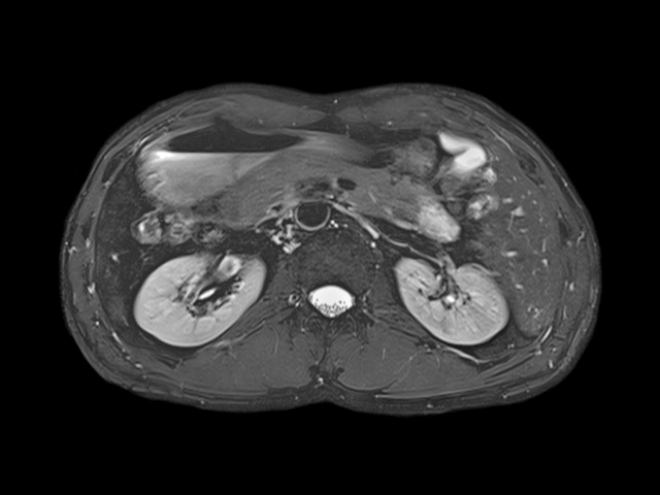

С другой стороны, магнитно-резонансная томография не использует ионизирующее излучение и предоставляет высококачественные изображения мягких тканей, что делает её предпочтительной для оценки сосудистых и опухолевых процессов. МРТ особенно полезна при необходимости изучения функционального состояния почек и выявления воспалительных заболеваний.

Разница в информативности КТ и МРТ состоит в том, что МРТ определяет даже незначительные изменения в почечной паренхиме и выявляет опухоли почек на самых ранних стадиях, а КТ , метод, позволяющий лучше визуализировать камни при мочекаменной болезни, что важно для предстоящей операции по их удалению или дроблению.

Негативного влияния на организм МР-аппаратуры не установлено, она исключает накопительный эффект, поэтому угрозы здоровью не несут даже сделанные за короткое время несколько процедур подряд. Детям МРТ проводят по строгим клиническим показаниям. При этом врач может предложить использовать наркоз.